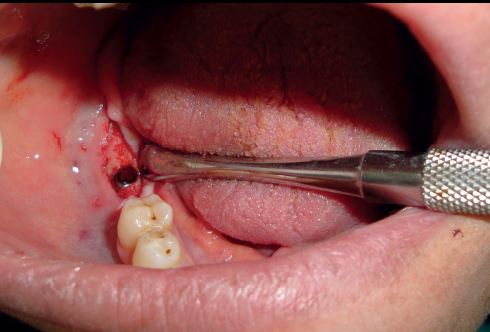

A vacuum stent surgical guide was made for each patient to be used during the surgery to determine the position of implant installation; Anesthesia (Inibsa Artinibsa 4%, Spain) was given, then the surgical guide was placed in the patient's mouth, and the probe was used to mark the proposed site for implant placement. A crystal incision was made extending 5 mm mesial and distal to the marked implant site. A full-thickness mucoperiosteal flap was reflected. The implant osteotomy of 10 mm length and 3.6 mm diameter was sequentially drilled, then the implant (Superline; Dentium, Korea) was installed in the osteotomy site (Fig. 2), and its cover screw was tightened, and the flap was sutured. After three months, the healing abutment was screwed to the implant and left for ten days for gingival healing and formation of the gingival collar and then replaced by the final abutment. The first and second premolar teeth in the distal extension side were reduced and prepared with sub-gingival finishing lines ready for crowing (Fig. 3). The final impression was made using a rubber base after changing the final abutment with impression-transfer (closed tray). Composite temporary (Protemp™ Plus, USA) crowns were made, then finished, polished, and cemented temporarily.

Fig. (2). The implant was installed in the osteotomy site.